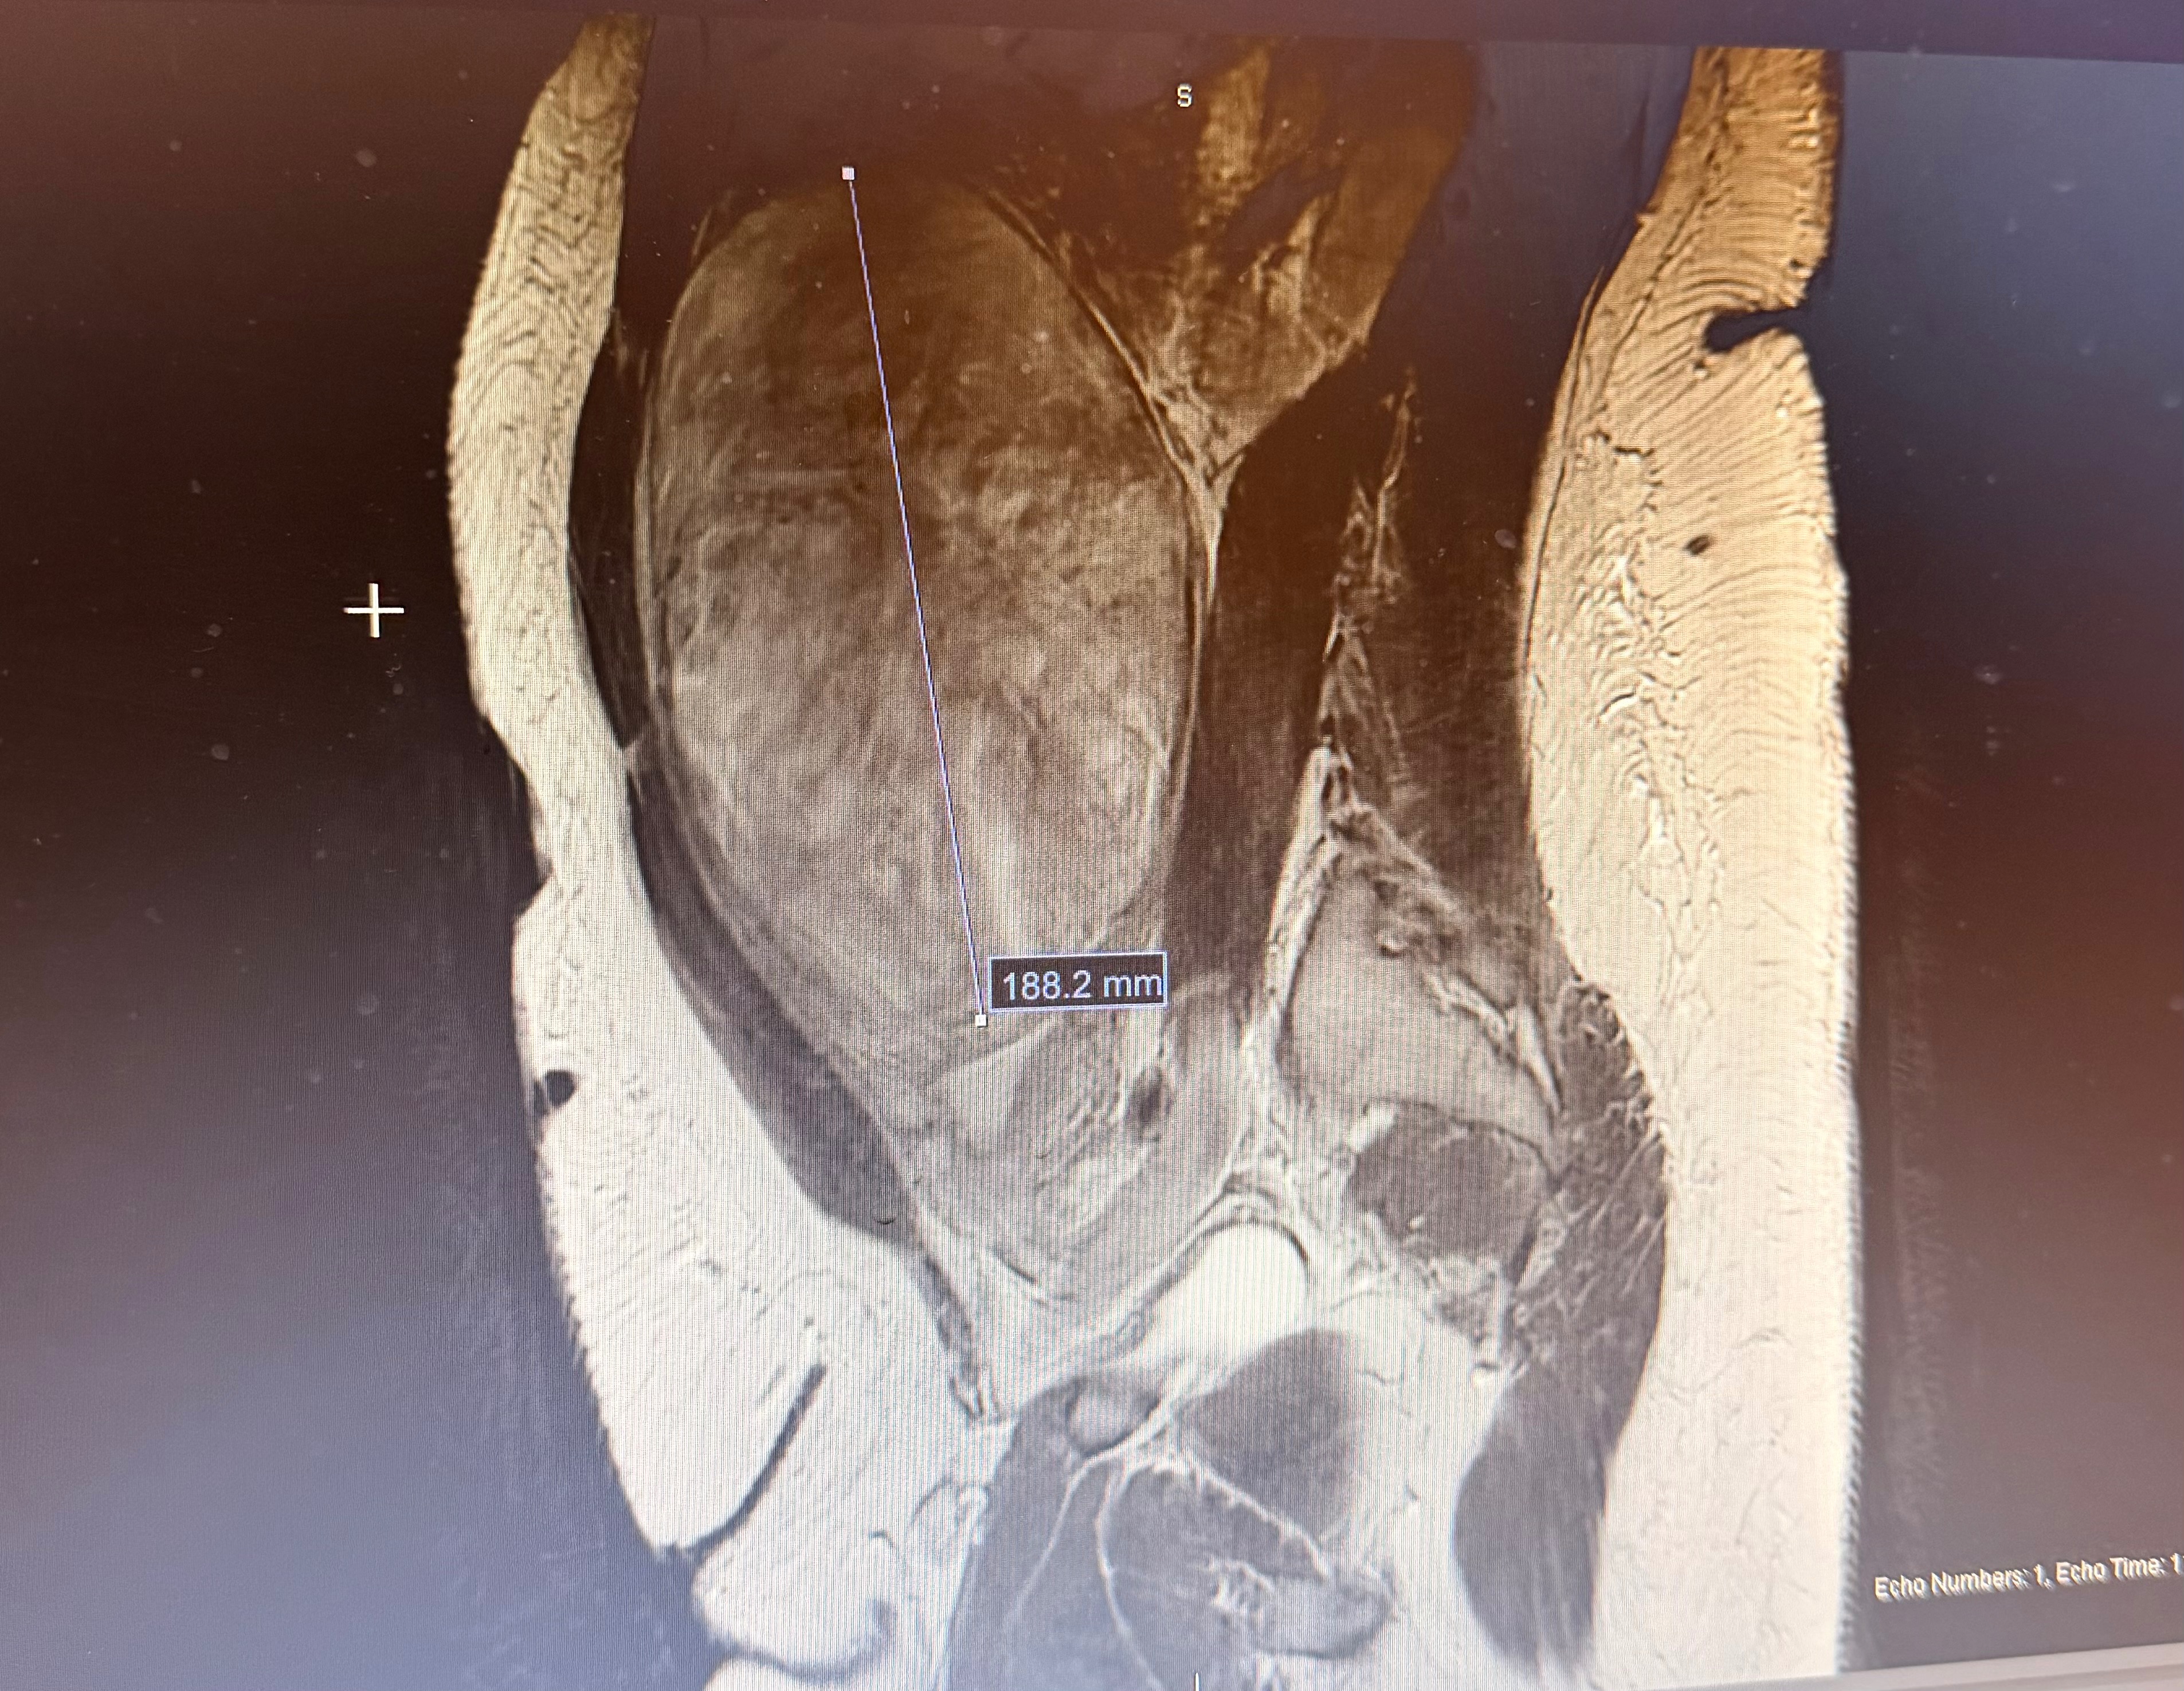

My friend Krystle is one of the most hard-working, passionate, and loving people I know. Recently, she received a difficult diagnosis: major fibroids, with one measuring the size of a seven-month pregnancy. This fibroid is pushing up on her internal organs, and if left untreated, it could become life-threatening. The condition has also made her anemia worse and is starting to interfere with her daily life and ability to function.